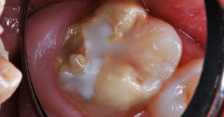

A resin-based composite had failed; the molar was sensitive, malformed, and carious.

Figure 20

A 7-year-old boy originally had resin-based composite repair of his severely malformed permanent molar elsewhere. Chronic tooth sensitivity followed, and the resin-based composite repair failed (Figure 20). The tooth was then restored with a preformed stainless steel crown with careful marginal trimming, crimping, finishing, and polishing, using the methods of Croll and Castaldi (Figure 21 through Figure 23).1,9 The crown is shown 18 months after treatment (Figure 24). This treatment was reported as Case 4 in a prior publication.4 Two years after crown placement, the mesial marginal ridge of the adjacent second molar engaged the distal margin of the stainless steel crown (Figure 25). An orthodontic band was pressed firmly into place over the steel crown, for 3 months, serving to distally reposition the second molar (Figure 26 and Figure 27).